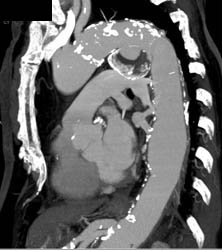

Metastatic Carcinoid With Implants on the Diaphragm